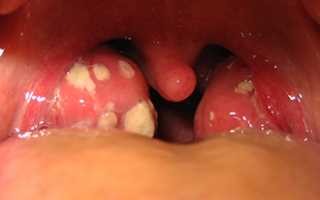

Хронический тонзиллит, хотя и локализован в области миндалин, влияет на весь организм. Люди, страдающие этим заболеванием длительное время, сталкиваются с различными последствиями хронической инфекции: астеническим синдромом, нарушениями работы сердца, сосудов и почек, а также сопутствующими заболеваниями, такими как парафарингит и паратонзиллярный абсцесс. Лечение следует начинать как можно раньше. Как избавиться от гнойных пробок в горле? Тактика терапии зависит от классификации форм хронического тонзиллита:

Если у пациента диагностирована токсико-аллергическая форма второй степени, то тонзиллэктомия становится единственным эффективным методом коррекции состояния. Степень тяжести патологических изменений увеличивается, и возникают новые осложнения. Миндалины теряют свои полезные функции и становятся очагом хронического воспаления и источником бактериальных токсинов, при осмотре обнаруживаются многочисленные казеозные пробки в горле.